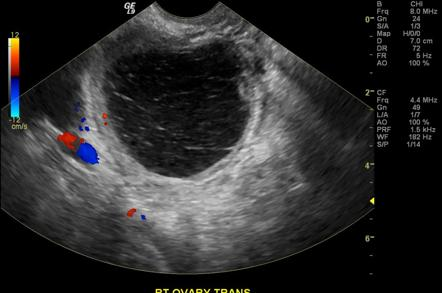

- Sonography (TAS or TVS):

- Thin walled

- Anechoid (filled with fluid)

- Echogenic material (clot in hemorrhagic cyst)

- Flow around margin of cysts in doppler (”Ring of fire” – corups luteum cyst)